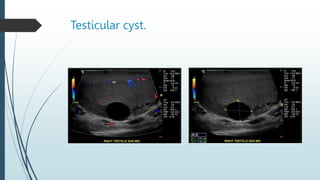

Testicular cyst.

Testicular cyst as with cysts elsewhere in

the body.

Testicular cysts are well defined, thin

walled and anechoic on ultrasound,

sometimes with distal acoustic

enhancement.

They are vary in size from a millimeter to

centimeter.

Occasionally multiple.

Cysts directly arising from the tunica

albuginea have been described with similar

features.

Testicular cysts are usually benign in nature.

Multiple small cystic areas are not infrequently

seen at the testicular hilum.